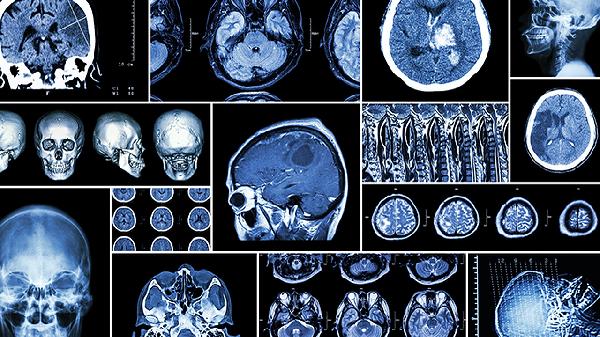

記錄日常活動后胸痛發作頻率及持續時間,夜間平臥是否出現呼吸困難。支架植入部位可能出現血管再狹窄,表現為運動后心前區壓榨感,需通過冠脈CTA復查評估。